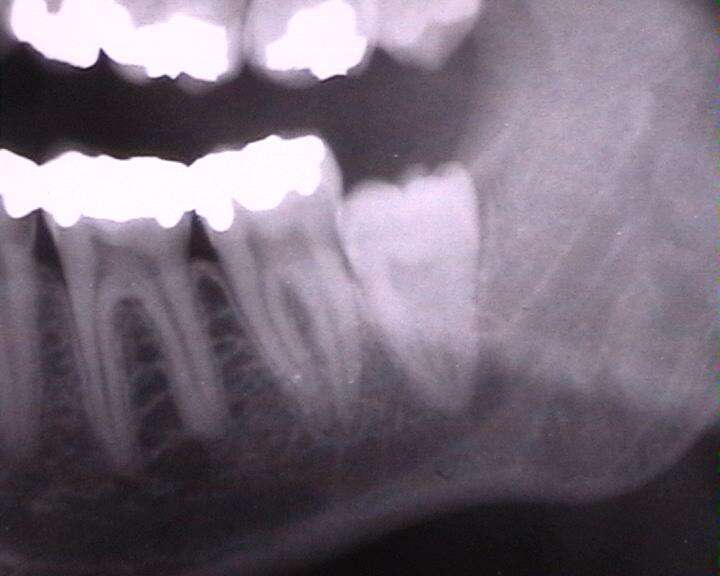

Ludzie z mniejszymi szczękami wyglądali lepiej, ale w ich buziach nie było miejsca dla kompletnego uzębienia. Ósemki stały się niepotrzebne, a wręcz uciążliwe, a jednak nie przestawały rosnąć. Ponieważ zęby mądrości wyrzynają się jako ostatnie, często dochodziło do sytuacji, w której zgryz był w pełni ukształtowany, a w szczęce nie było miejsca dla więcej niż 28 zębów. W efekcie, ósemki nie mogły wydostać się z kieszonki zębowej i zaczynały rosnąć pod niewłaściwym kątem. Taka wada dotyka dzisiaj aż 65% ludzi na całym świecie. Tylko u nielicznych zęby mądrości nie wyrzynają się wcale.

Zablokowanie ósemek oznacza duży ból, a także ryzyko infekcji. Do zębów mądrości nie jesteśmy w stanie dotrzeć podczas codziennego szczotkowania, więc zaczynają one po prostu próchnieć. Komplikacje mogą być różnorodne – od zapaleń, przez uszkodzenie dziąseł, parodontozę, po zdeformowanie zgryzu. Lekarze nierzadko trafiają na pacjentów z problemami z sercem, którzy – jak się okazuje po dogłębnej diagnostyce – mają chore zęby.